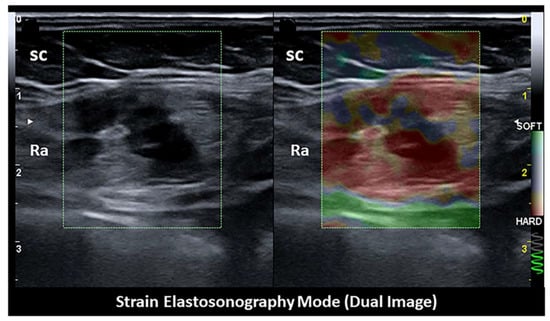

- Xie, M.; Zhang, X.; Zhan, J.; Ren, Y.; Wang, W. Potential role of strain elastography for detection of the extent of large-scar endometriosis. J. Ultrasound Med. 2013, 32, 1635–1642. [Google Scholar] [CrossRef]